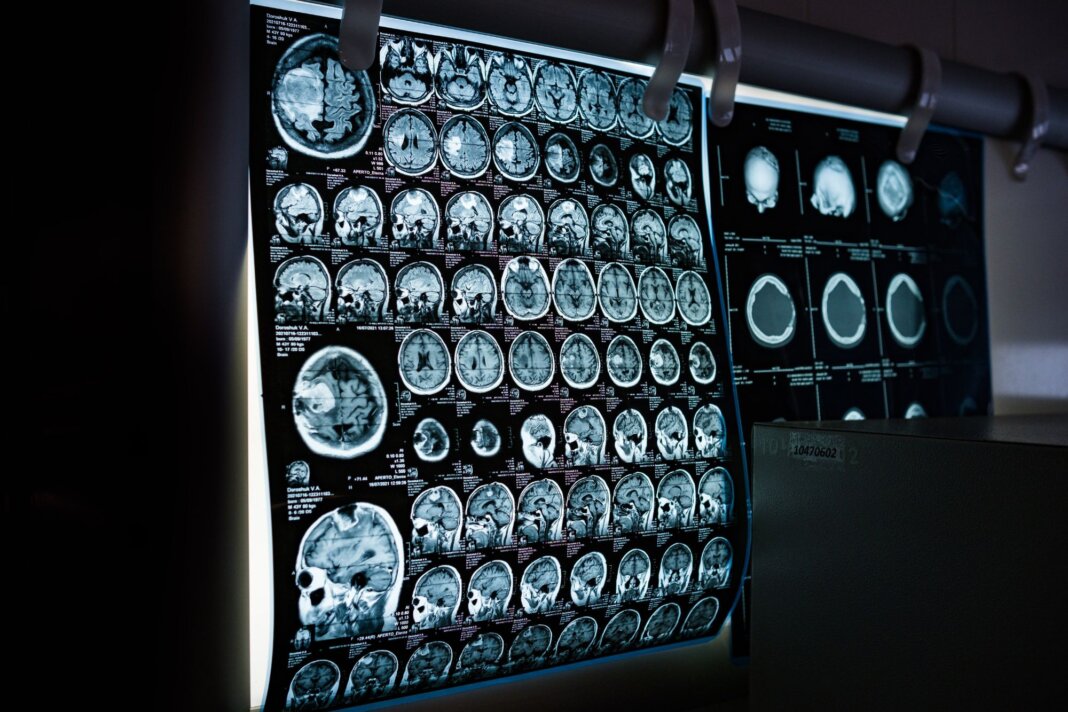

L’atlante da un milione di cellule

Lo studio, guidato da Alex R. DeCasien del National Institute of Mental Health, rappresenta una novità per le neuroscienze. I ricercatori hanno analizzato circa 1,2 milioni di cellule provenienti da sei diverse regioni della corteccia cerebrale di 30 donatori. Grazie a tecnologie di trascrittomica, la disciplina biologica che studia l’insieme completo degli Rna messaggeri presenti in una cellula, tessuto o organismo a singola cellula, il team ha potuto osservare l’attività di 680.000 neuroni eccitatori, 290.000 neuroni inibitori e centinaia di migliaia di cellule gliali, le instancabili “assistenti” del cervello.

Il risultato è una mappa ad altissima risoluzione che identifica dove e come i cromosomi sessuali e gli ormoni lasciano la loro impronta molecolare.